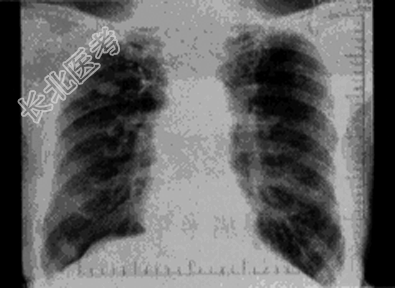

- 单项选择题患者男,69岁, 胸闷气促多年,近来咳嗽, 无胸痛、无痰中带血,X线检查如图, 最可能的诊断是

A、慢支肺气肿、右上肺肿瘤

B、慢支肺气肿、右上肺炎性假瘤

C、慢支肺气肿、右上肺结核瘤

D、慢支肺气肿、肺转移瘤

E、慢支肺气肿、结节病